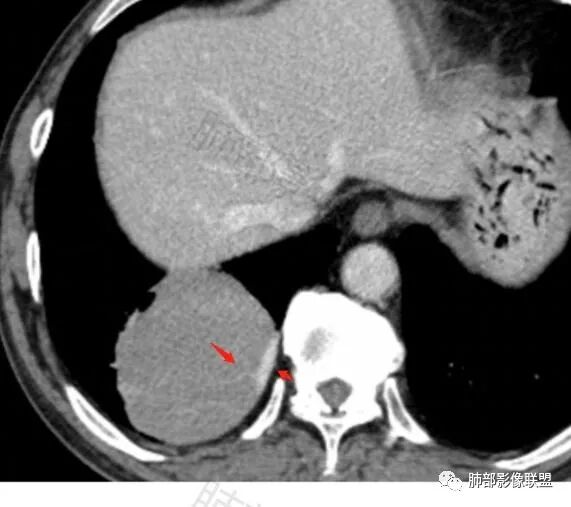

右肺下叶肿块,呈外带大内带小的椭圆形改变(内带受支气管及血管挤压原因),边缘光滑,无分叶毛刺,支气管受压,增强后,均匀延迟强化,动脉期见血管贴边,静脉期内部瘤样血管强化区,相邻胸膜无侵犯,纵隔无淋巴结肿大,符合PSP,不鉴别。

胸部CT:右肺下叶一类圆形肿块影,边界清楚,大部分边缘光滑、外缘边界模糊,邻近支气管推移、血管贴边,病灶内可见分枝状血管,平扫密度尚均匀,增强后大部分均匀延迟强化,部分与膈肌黏连、尾征?考虑:类Ca>PSP>SFT。鉴别肉瘤样Ca,CD等。

肿块位于周围(起自细支气管呼吸道上皮),均匀膨胀生长(符合良性的生长特点),病灶内部大部分密度较均匀,部分小低密度不强化区(囊变),增强强化较明显,边缘血管增粗贴边,临近支气管受压,支持PSP。

常规肿瘤如果背侧胸膜来源,肿瘤与胸膜之间不应该夹杂含气支气管,会推移

但是肺内可以将支气管外推,夹在胸膜之间

与膈面胸膜类似推断

支持肺内

但是这条血管需要交代一下:

如果这是同一根肺动脉,支持PSP

因为肺门区来源肺动脉

还是需要观察到支气管才行